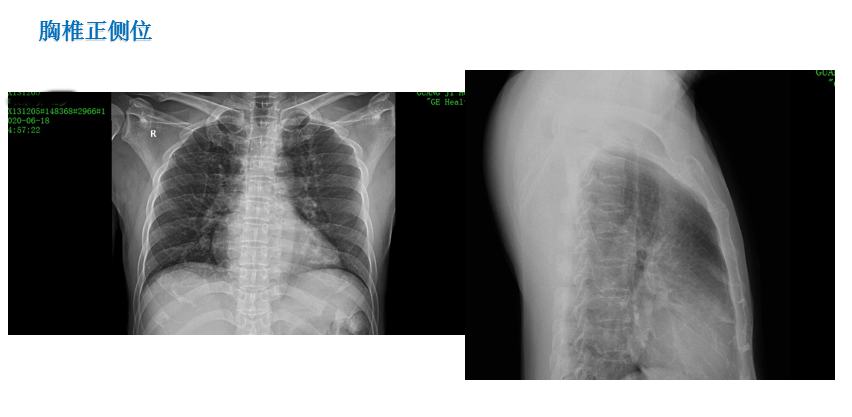

患 者:李某,男,42岁。

主 诉:因摔伤致腰背部、右跟部疼痛伴活动受限2小时,入院治疗。

症 见:患者从2米高处摔下,双足着地,即觉腰背部、右跟部疼痛伴活动受限,受伤当时无胸闷气促,无恶心呕吐。

专科检查:胸腰椎稍后突,胸腰部稍肿胀,无瘀青,皮肤黏膜完整,腰1、2棘突处轻压痛,腰2椎旁轻压痛,局部叩痛,双侧沿坐骨神经区无压痛,右大腿前中部感觉减退。双大腿内侧、内踝、第3跖趾关节背侧、足跟外侧感觉无减退。肛门反射存在,双侧膝反射、双侧踝反射消失。髂腰肌肌力(Ⅴ级)。双侧股四头肌肌力(Ⅴ级),双侧胫骨前肌肌力(Ⅴ级),双侧踇长伸肌肌力(Ⅴ级),双侧踇长屈肌肌力(Ⅴ级),双侧踝关节跖屈(小腿三头肌)肌力(Ⅴ级)。直腿抬高试验(-)、加强试验(-),拾物试验(不能配合完成)。腹壁反射、肛门反射正常。右肾区叩击痛(+),左肾区叩击痛(-),输尿管移行区无叩击痛。左髋部叩击痛,髋关节活动可,4字征(-)。右外踝、跟部肿胀,皮肤黏膜完整,局部可见皮下淤血,压痛,未触及骨擦感,足背动脉可及,右足末梢感觉无减退,右踝外侧应力试验、抽屉试验不能配合,右踝关节主动活动稍受限,右足各趾活动可。

影像资料:

诊 断:

1:腰1、2椎体压缩骨折(椎体分别压缩约40%、10%);

2:腰椎退行性改变伴椎管狭窄;

3:腰3/4、4/5、腰5/骶1椎间盘膨出;

4:右跟骨骨折;

5:胸12陈旧性骨折。